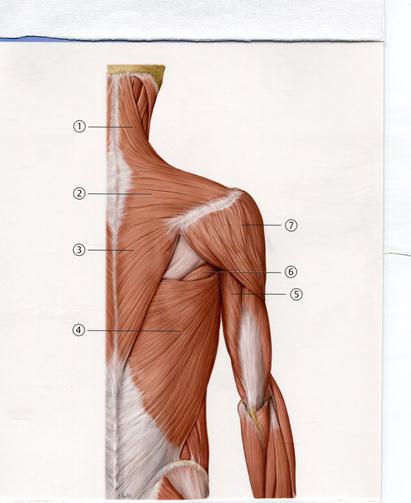

D. Медиальді айдаршық буын беті

D. Ортаңғы милық

49. Төменде көрсетілген суреттегі белгіленген № 3 бұлшықетті атаңыз.

Е. Үлкен жұмыр